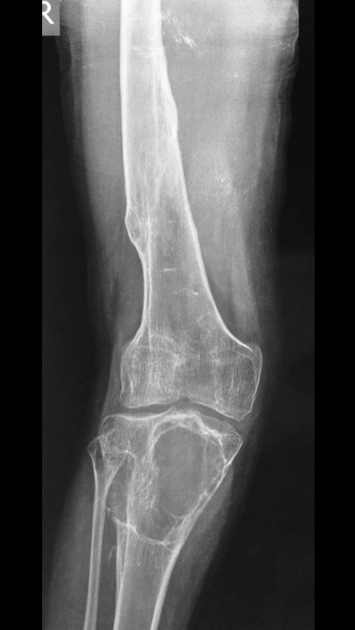

U tế bào khổng lồ của xương (Giant Cell Tumor - GCT of bone)